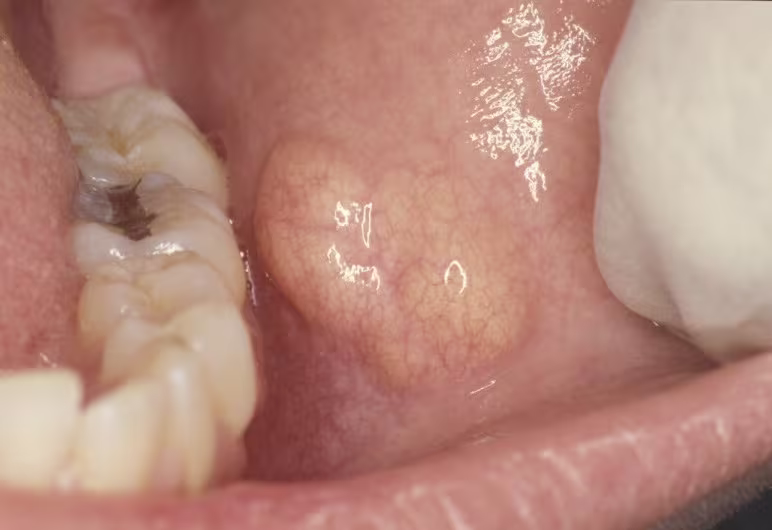

Pregnant Female with “Bump” in Cheek

Can you make the diagnosis? A 32-year-old gravid female with bumps in her cheek.